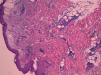

Caso clínicoVarón de 70 años, sin antecedentes de interés, que presentaba episodios recurrentes de 2 semanas de duración de fiebre alta, leucocitosis y pápulas y placas eritematosas en extremidades, que mostraron densos infiltrados neutrofílicos en la biopsia realizada (fig. 1). El paciente presentaba oligoartritis asimétrica que afectaba una muñeca y las rodillas. Analíticamente, se observó una velocidad de sedimentación (VSG) elevada, leucocitosis y anemia. Se trataron los episodios con glucocorticoides a dosis de 0,5mg/kg de peso, con escasa respuesta. La enfermedad se hizo crónica y recurrente. Se pautó indometacina a dosis de 150mg/día y yoduro potásico, sin observar mejoría. Paralelamente, el paciente fue diagnosticado de una AREB tipo 1 a raíz del estudio de una anemia persistente. Se le realizaron múltiples transfusiones de hematíes.